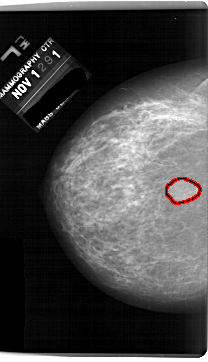

A_1691_1.RIGHT_MLO

RIGHT_CC LINES 6151 PIXELS_PER_LINE 3556 BITS_PER_PIXEL 12 RESOLUTION 43.5 NON_OVERLAY

FILE: A_1691_1.LEFT_CC.OVERLAY

TOTAL_ABNORMALITIES 1

ABNORMALITY 1

LESION_TYPE MASS SHAPE LOBULATED MARGINS CIRCUMSCRIBED

ASSESSMENT 4

SUBTLETY 4

PATHOLOGY BENIGN

TOTAL_OUTLINES 1

BOUNDARY